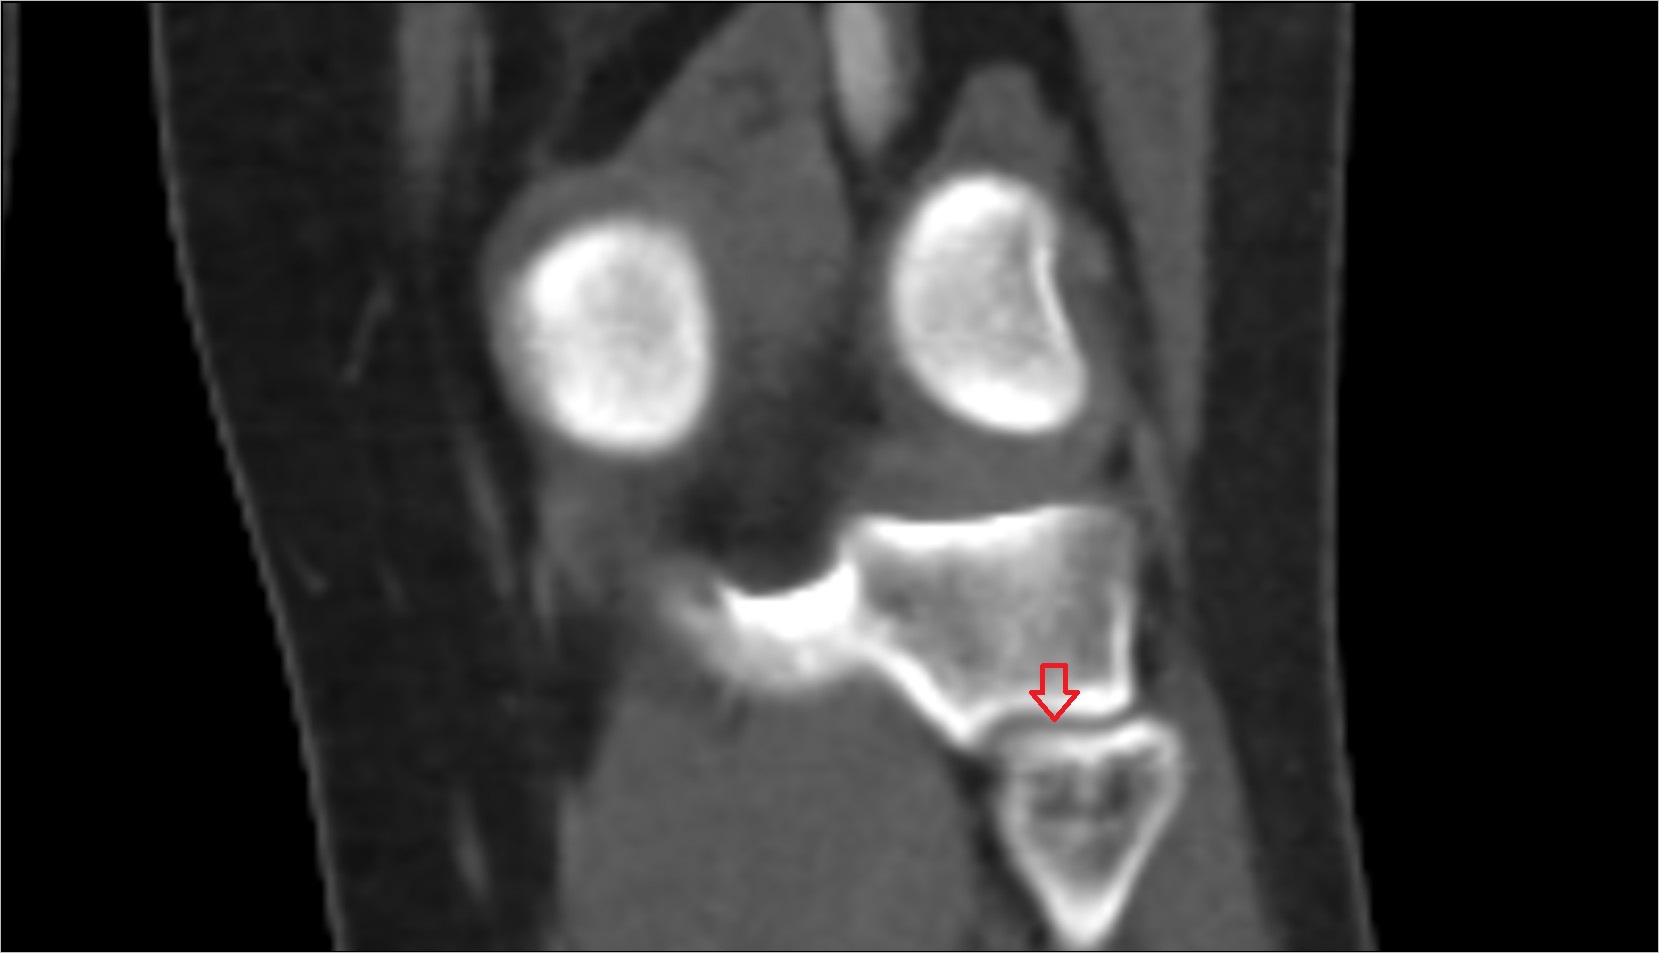

- Knee Joint